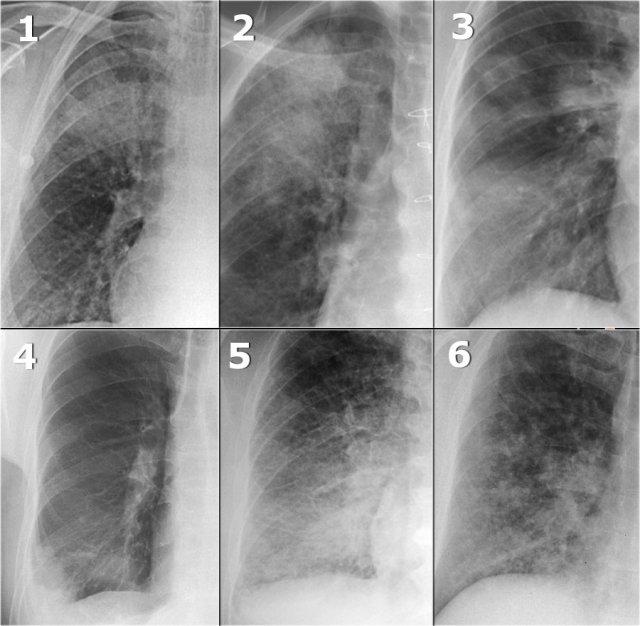

Đây là một số X-quang có hình ảnh đông đặc.

Lưu ý sự tương đồng giữa các X-quang ngực này.

- Viêm phổi thùy – ở bệnh nhân có ho và sốt.

- Xuất huyết phổi – ở bệnh nhân có ho ra máu.

- Viêm phổi tổ chức hóa (OP) – đông đặc mạn tính đa ổ.

- Nhồi máu – đông đặc ngoại vi ở bệnh nhân khó thở cấp tính với mức oxy thấp và D-dimer cao.

- Phù phổi do tim – lấp đầy phế nang bằng dịch thấm ở bệnh nhân suy tim sung huyết. Điều này sẽ rõ ràng hơn nếu được xem toàn bộ hình ảnh.

- Sarcoidosis – thoạt nhìn trông giống đông đặc, nhưng thực ra đây là bệnh phổi kẽ dạng nốt lan rộng đến mức trông giống như đông đặc.